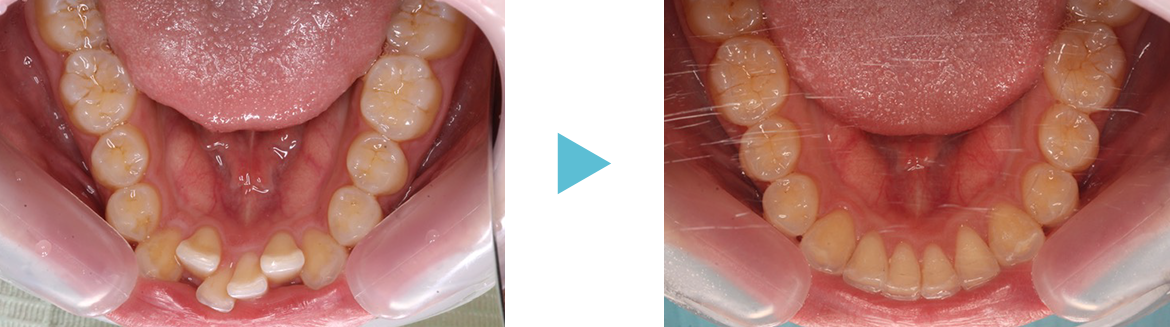

歯並びが混み合っている原因は歯の大きさに対して歯列(顎の大きさ)が小さいことが多いです。

硬いものをよく噛んでいれば顎が成長するのでしょうが、柔らかいものを食べている私たちは顎が小さくなっています。そこで歯列を大きくする拡大装置を使って歯列全体を大きくして永久歯が綺麗に並ぶように治療します。